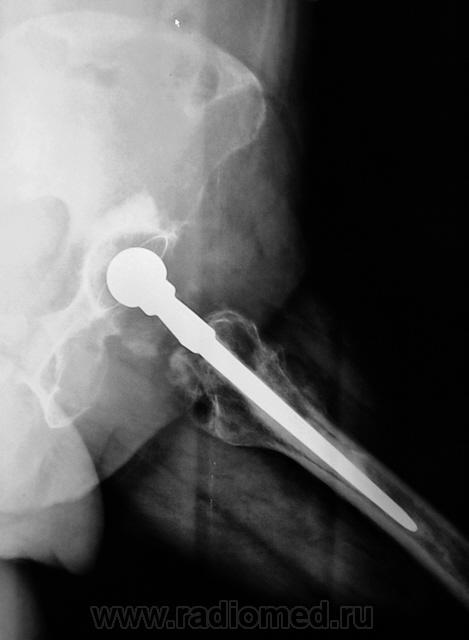

Шарнирный эндопротез. Пластиковая чашка установлена (по-моему правильно) в очищенной от суставного хряща вертлужной впадине и зафиксирована при помощи костного цемента. Ножка протеза в порядке. Какие-то остеофиты на латеральном контуре бедра (мелко: плохо видно).